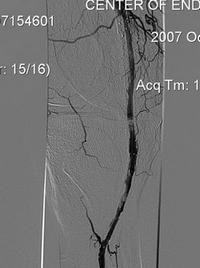

Пациент П, 1951 г.р. (56 лет).

- Атеросклероз.

- Окклюзия правой подколенной артерии и артерии правой голени.

- Сахарный диабет.

В мае 2007 г. произведена реканализация правой подколенной артерии, правого ТПС и правой ПББА со стентированием.

Тромбоз зоны стентирования в сентябре 2007 г.